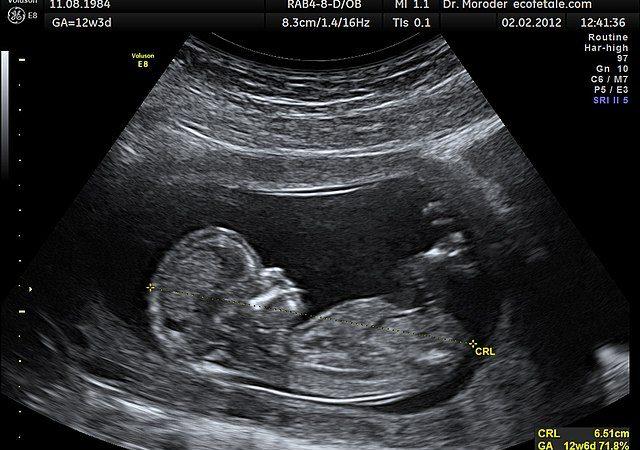

سونوگرافی جنین

در یک بارداری بدون مشکل حداقل سه بار سونوگرافی توصیه می شود :

سه ماهه اول بارداری 6-8 * هفته تعیین زمان زایمان

سه ماهه دوم بارداری 11-14 * هفته جهت غربالگری

بیماری های کروموزومی NB وNT

انجام سونوگرافي هاي تخصصي توسط متخصصين برجسته كشوري در زمينه سلامت جنين به شرح زیر انجام می شود:

سونوگرافی سه بعدی و چهاربعدی

18-24 هفته (بررسی سلامت جنین)

جهت تشخیص برخی ناهنجاری های جنینی از قبیل شکاف کام و ناهنجاری های ستون فقرات